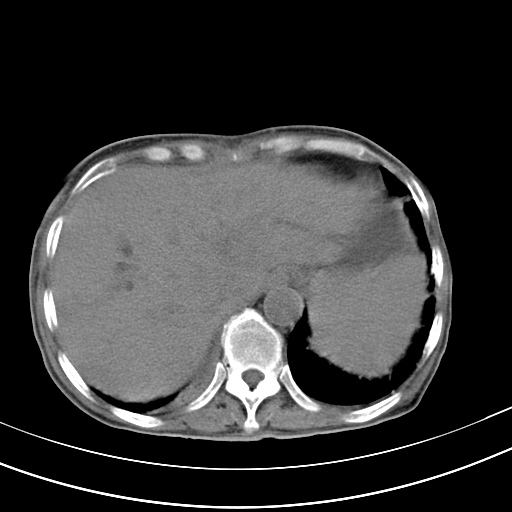

病人上腹部胀痛拌全身黄染八天

右侧少量胸水,胆囊增大,肝内胆管扩张,肝门部结构杂乱,建议增强。

右侧胸腔少量积液,右下叶结节灶,。

肝内胆管及胰管扩张考虑为胰头区占位,肝门淋巴结增多,肝内多发低密度影,考虑为转移。门脉高压,脾大,胆囊大。

肝内胆管及胰管扩张,胰头增大考虑为胰头区占位,肝门淋巴结增多,考虑为转移。建议增强,脾大,胆囊大,壁厚,慢性胆囊炎。胃壁好像也增厚,且有一肿物。

1)考虑胰头癌并胆系低位梗阻;建议行ct增强扫描检查。2)慢性胆囊炎。3)脾大。4)少量腹水。5)双侧少量胸腔积液。